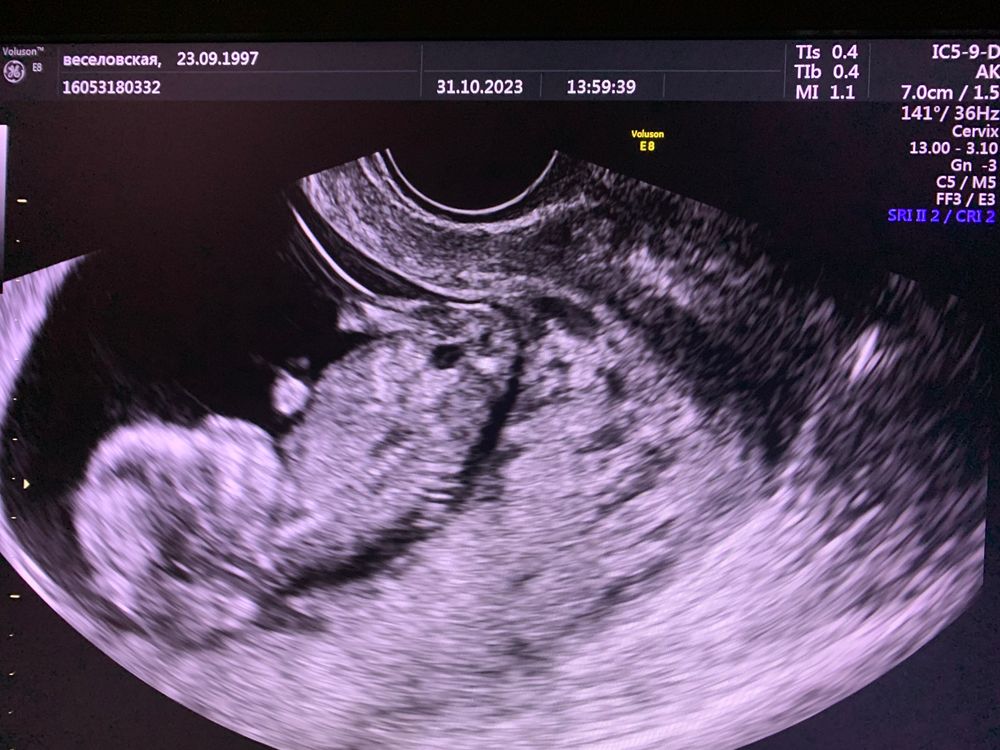

Скрининг 19 Недель Фото

Скрининг 19 Недель Фото 120 фото

13 14 Недель Беременности Фото